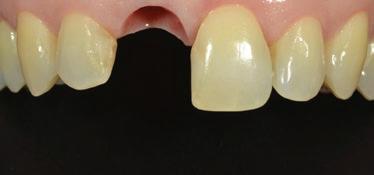

Cette formation de deux jours a pour objectif de vous permettre de diagnostiquer, planifier et réaliser des restaurations implantaires, tant unitaires qu’en édentation partielle fixe impliquant deux implants ou plus. Le contenu aborde les fondements essentiels de la restauration sur implant, ainsi que des notions plus avancées en implantologie prothétique.

Vous verrez l’ensemble des étapes cliniques — de la planification au suivi post-insertion — dans le but d’obtenir des restaurations fonctionnelles, esthétiques et durables. Vous aurez également l’opportunité d’observer des cas cliniques en direct, tant chirurgicaux que prothétiques, réalisés sur des patients, depuis la salle de cours ou la salle de traitement grâce à une retransmission vidéo en temps réel.

Temporisation en région antérieure